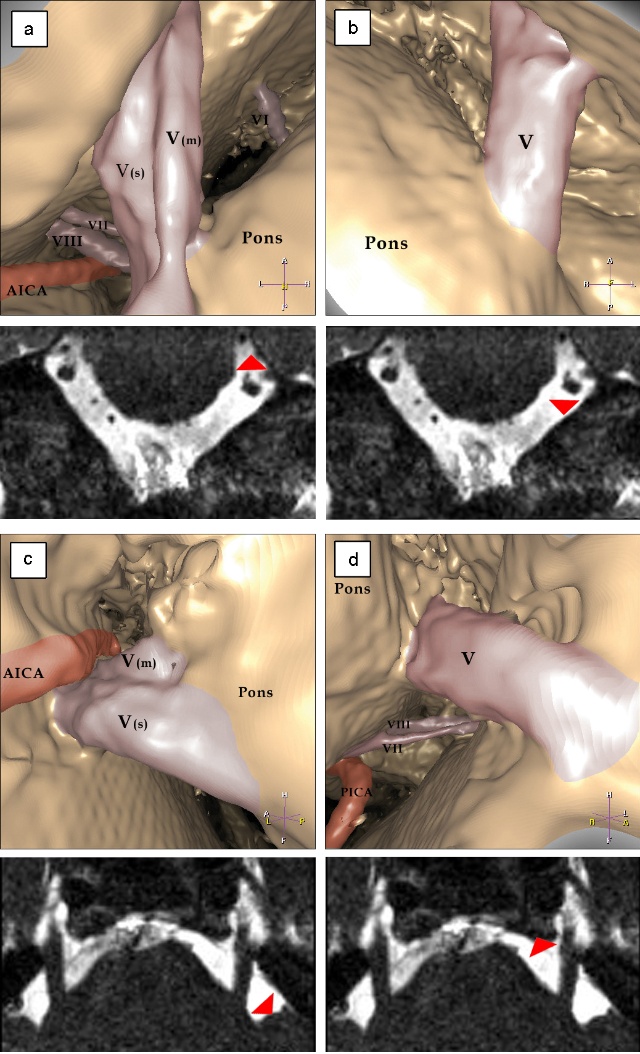

3. 三叉神经根受压的判断观察血管与三叉神经的解剖关系,由于侧卧位可引起小脑动脉移位,因此距三叉神经根1~2mm的血管均视为与神经有接触,特别是神经上有压迹或神经被推移和扭曲者更是可靠证据。下面部疼痛患者,是由于三叉神经根上前或后部受小脑上动脉压迫;而上部疼痛者则为神经根下外部受小脑前下动脉压迫。

4. 微血管减压确认血管压迫三叉神经根后,用长柄微型剥离子把血管从神经上分开,在三叉神经前方垫入小块明胶海棉。取1cm×0.5㎝涤纶片,两端用剪刀修成锐角,在明胶海绵和三叉神经根之间插入,并向后环绕神经,用一枚银夹把涤纶片两端对合,使之如“领套”状围绕桥脑旁的三叉神经, 以便与周围的血管隔离。也可用涤纶片衬垫在血管和神经之间,生物胶固定之。